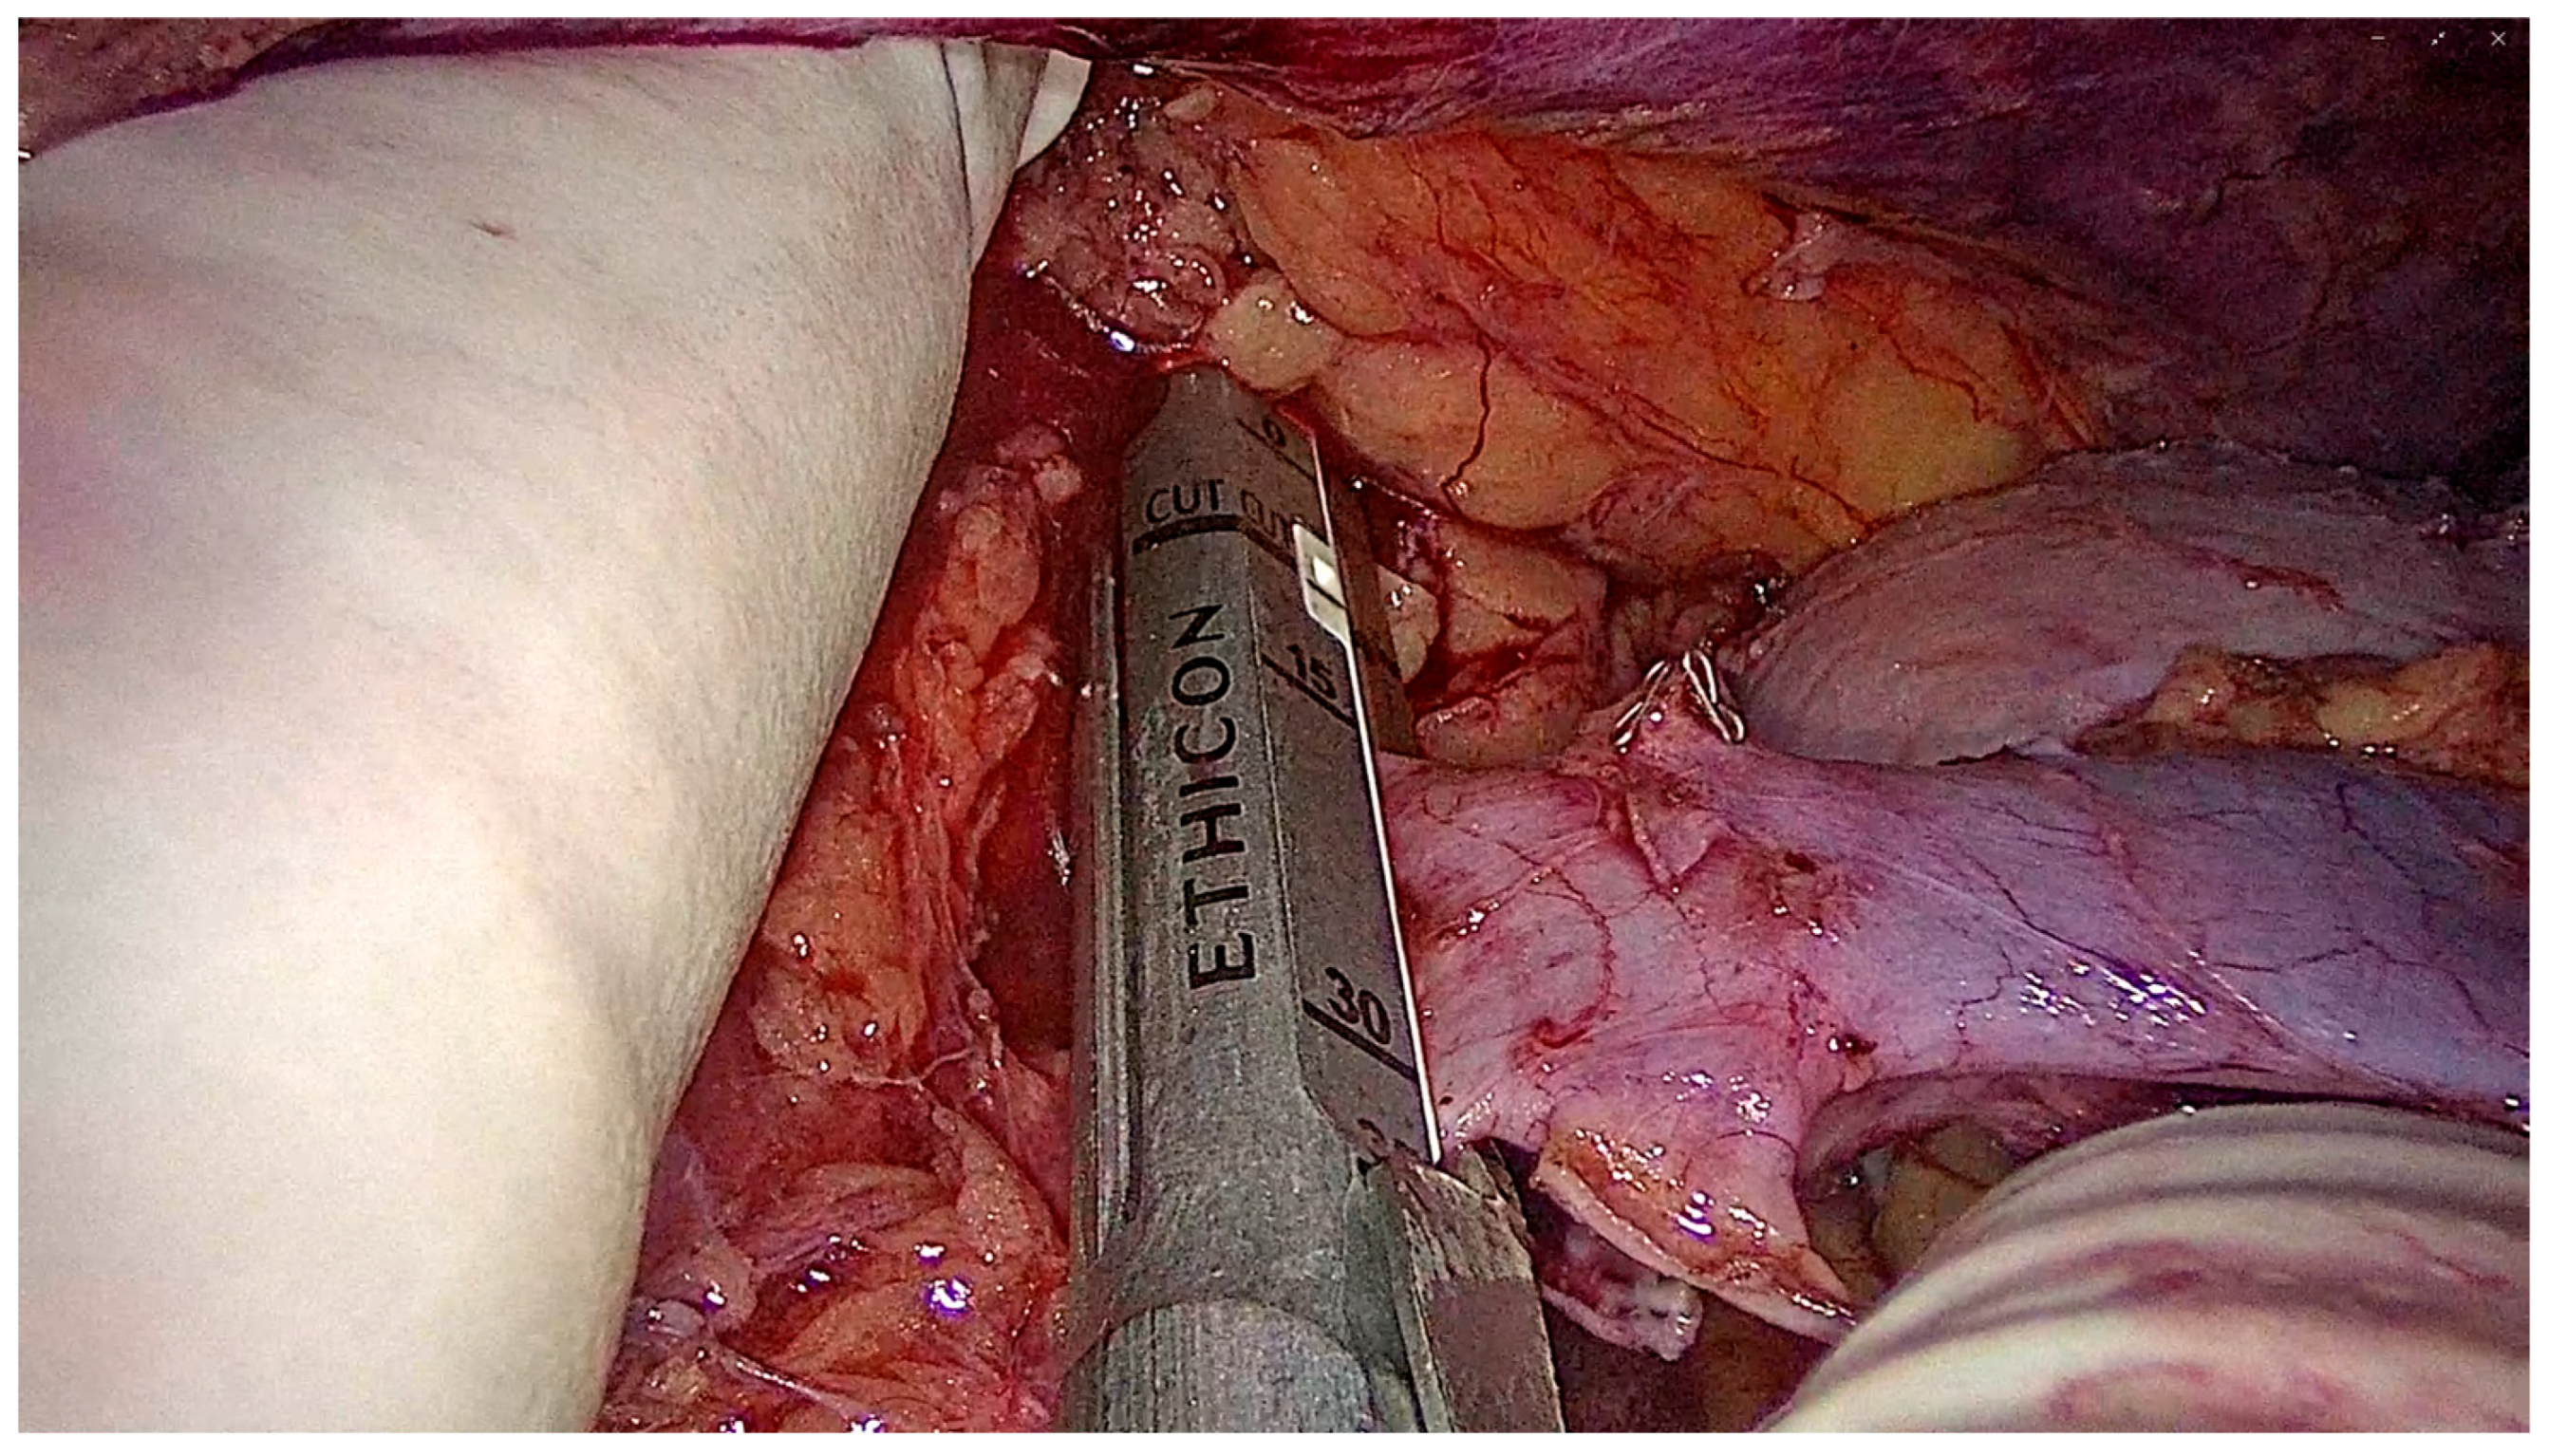

2.6.4. Graft Procurement and Extraction